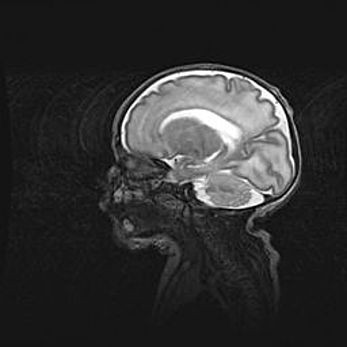

Неполная лизэнцефалия (пахигирия). Открытая гидроцефалия.

Возраст: 17 дней

Вес: 3110 г

Пол: мужской

Окружность головы: 33,5 см

Срок гестации: 35-36 недель

Лизэнцефалия—недоразвитие корковой пластинки и мозговых извилин в результате нарушения миграции нейронов коры. Поверхность мозговых полушарий гладкая. Микроскопически выявляется отсутствие нормальных слоев коры и скопление групп нейронов в подкорковом белом веществе.

Пахигирия—уменьшение числа вторичных извилин. В пораженном полушарии нервные клетки образуют толстый недифференцированный слой с неправильно расположенными нервными волокнами и группами гетеротопных клеток. Нервные клетки незрелые. Белое вещество истончено. При этом нередко аномально развит корково-спинномозговой путь.